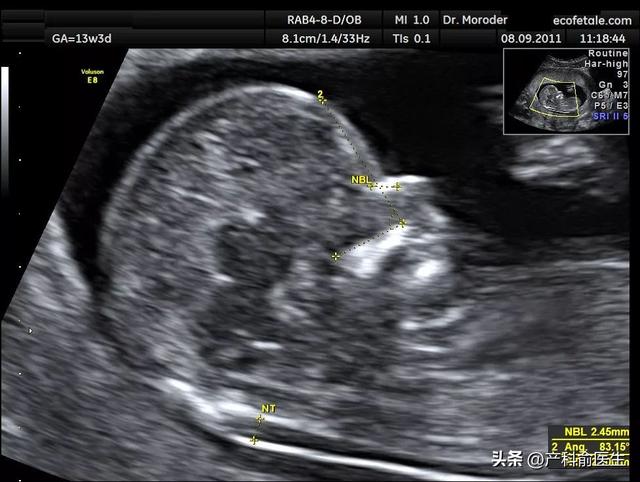

NT(Nuchal Translucency)透明带测量,是指在孕11-13+6周之间,通过超声检查测量胎儿颈部皮下透明层的厚度。

检查时间:孕11-14周;

检查目的:评估胎儿染色体异常风险(如唐氏综合征);主要观察:胎儿颈后透明层厚度、鼻骨、静脉导管、心脏等结构;不是设计来判断性别的检查。那NT能看出性别吗?

在NT阶段,由于胎儿生殖器官尚未完全分化,性别判断非常不准确。

不过有些熟练的超声医生会通过“尿生殖突(nub theory)”预测性别,但:只能看“趋势”;

准确率仅约60%-70%;不具诊断意义,也不做正式报告。一般在怀孕16周左右才真正看清楚。